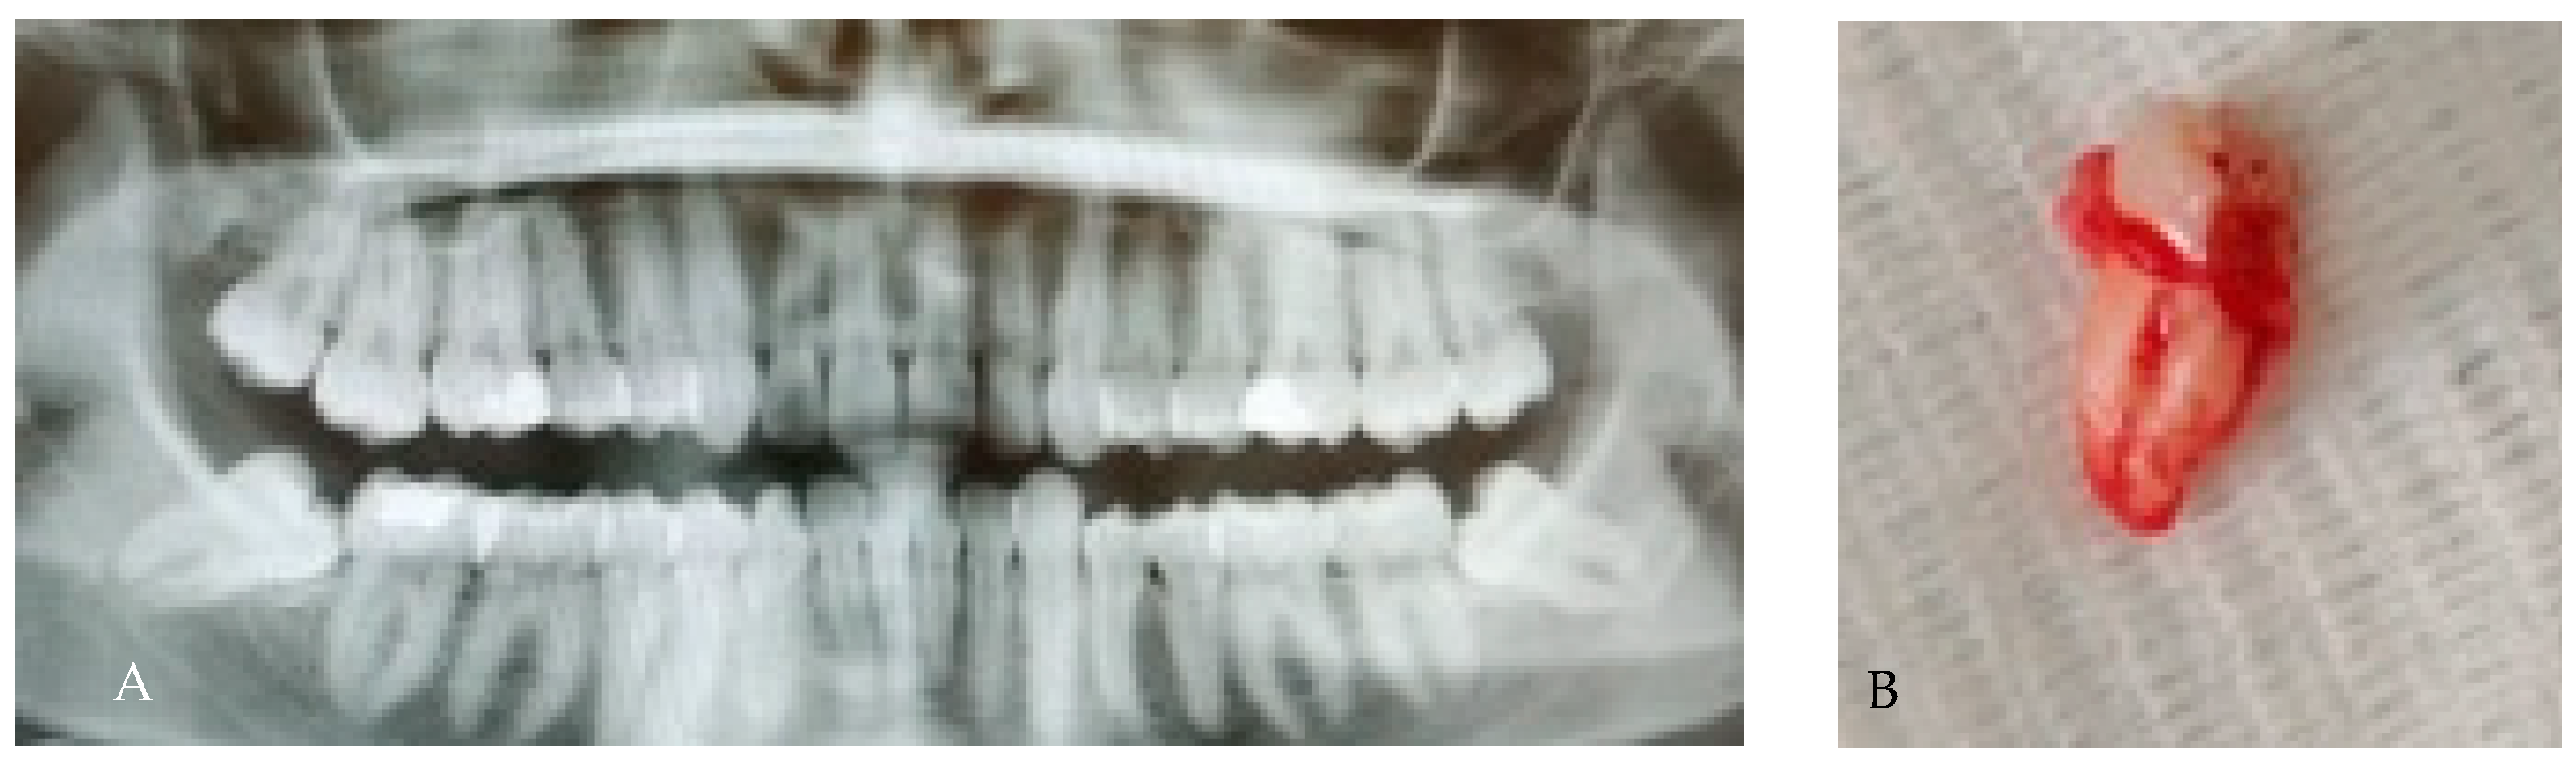

3.7. Dilaceration/Apical Curvature

| Position/Orientation | Dilaceration | Curved or hooked apices | Impedes straight-line removal; risk of apical fracture; consider apex-first retrieval |

| Dilaceration | Curved or hooked root apex (>20–40°) | 10–22% | Impedes straight-line removal; risk of apical fracture; may require coronectomy or apex-first approach | [8,9] |

| Dilaceration | 10–22% | Apex-first retrieval; coronectomy if near IAN | [8,9] |